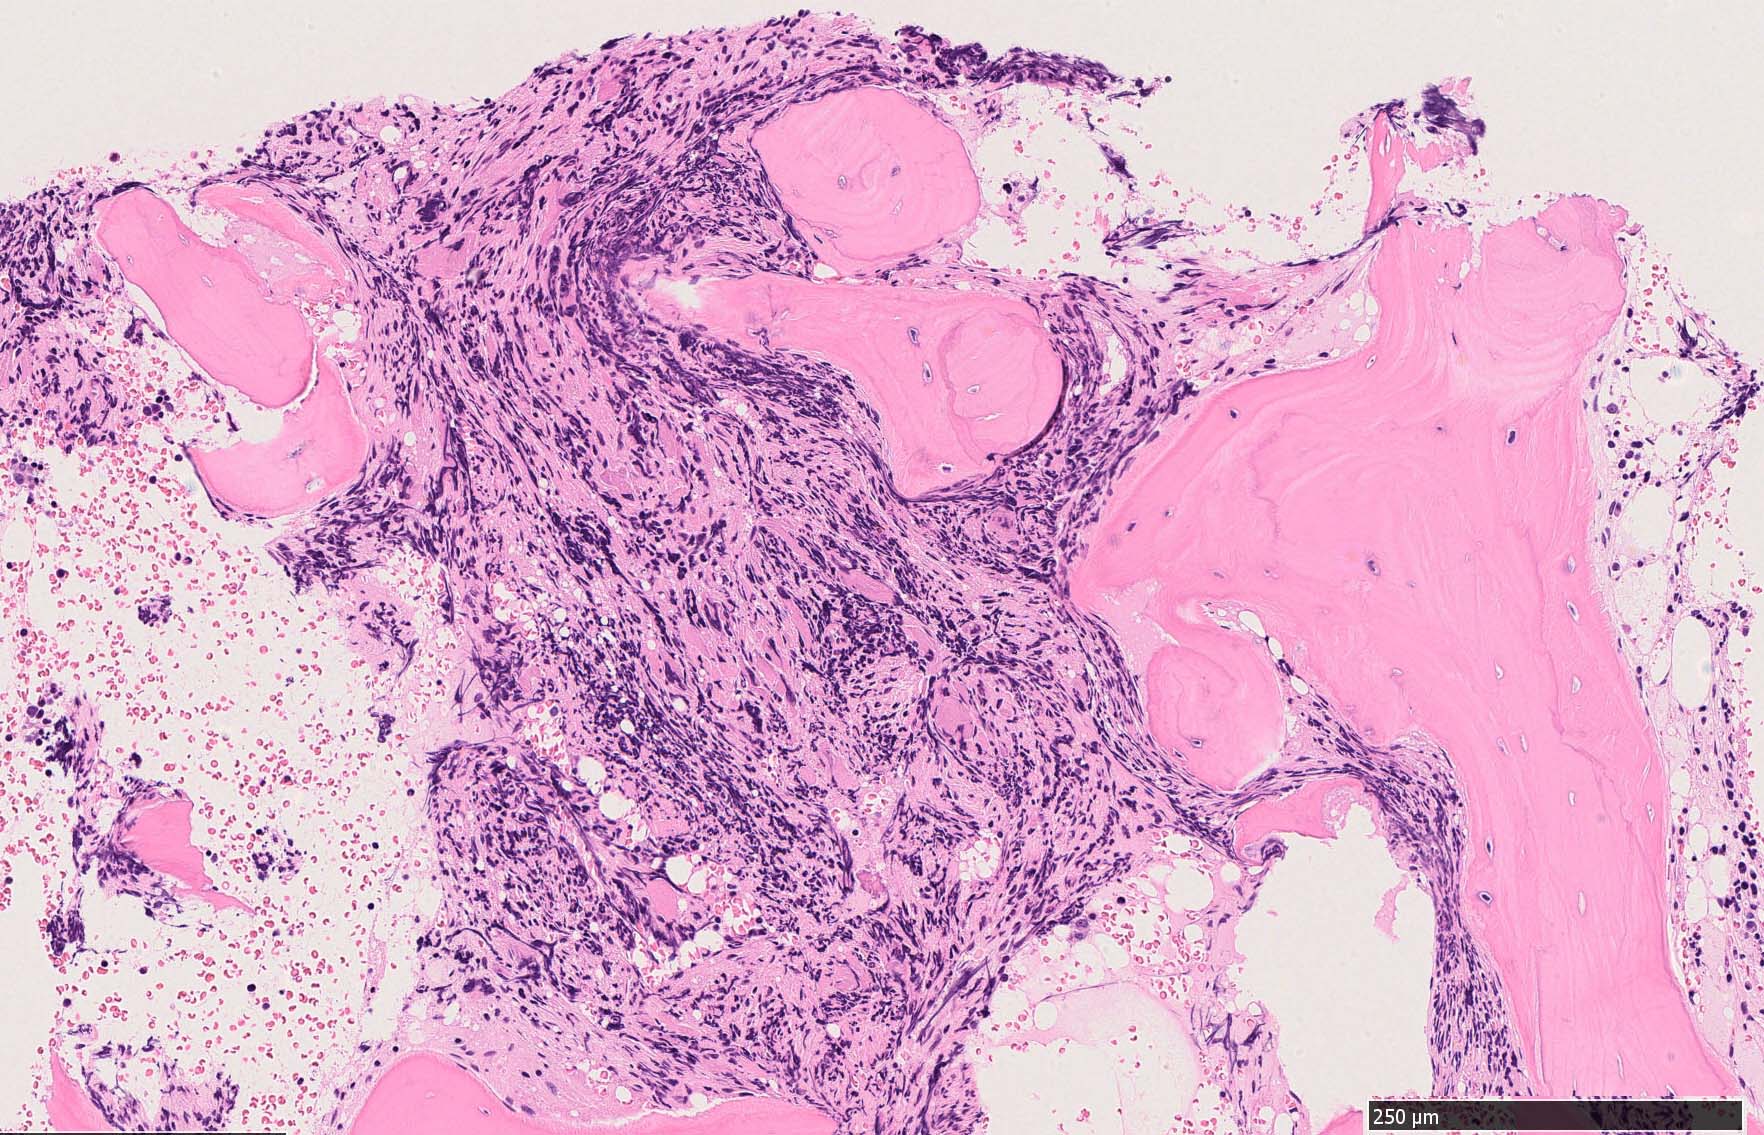

Case02; Meylofibrosis, overt fibrosis

77year-old female. 40歳時polycythemia veraと診断されていた.

[注] この症例は詳細は不明であるが, 過去にPVと診断されているため, PVに伴う二次性のmyelofibrosisの診断になる.

黒染する弾性線維の増生のほか, 赤く染まる膠原線維の増生が確認される. MF-2 fibrosis. 鍍銀染色の核染色をすると膠原線維の赤染がわからなくなるので行わない.